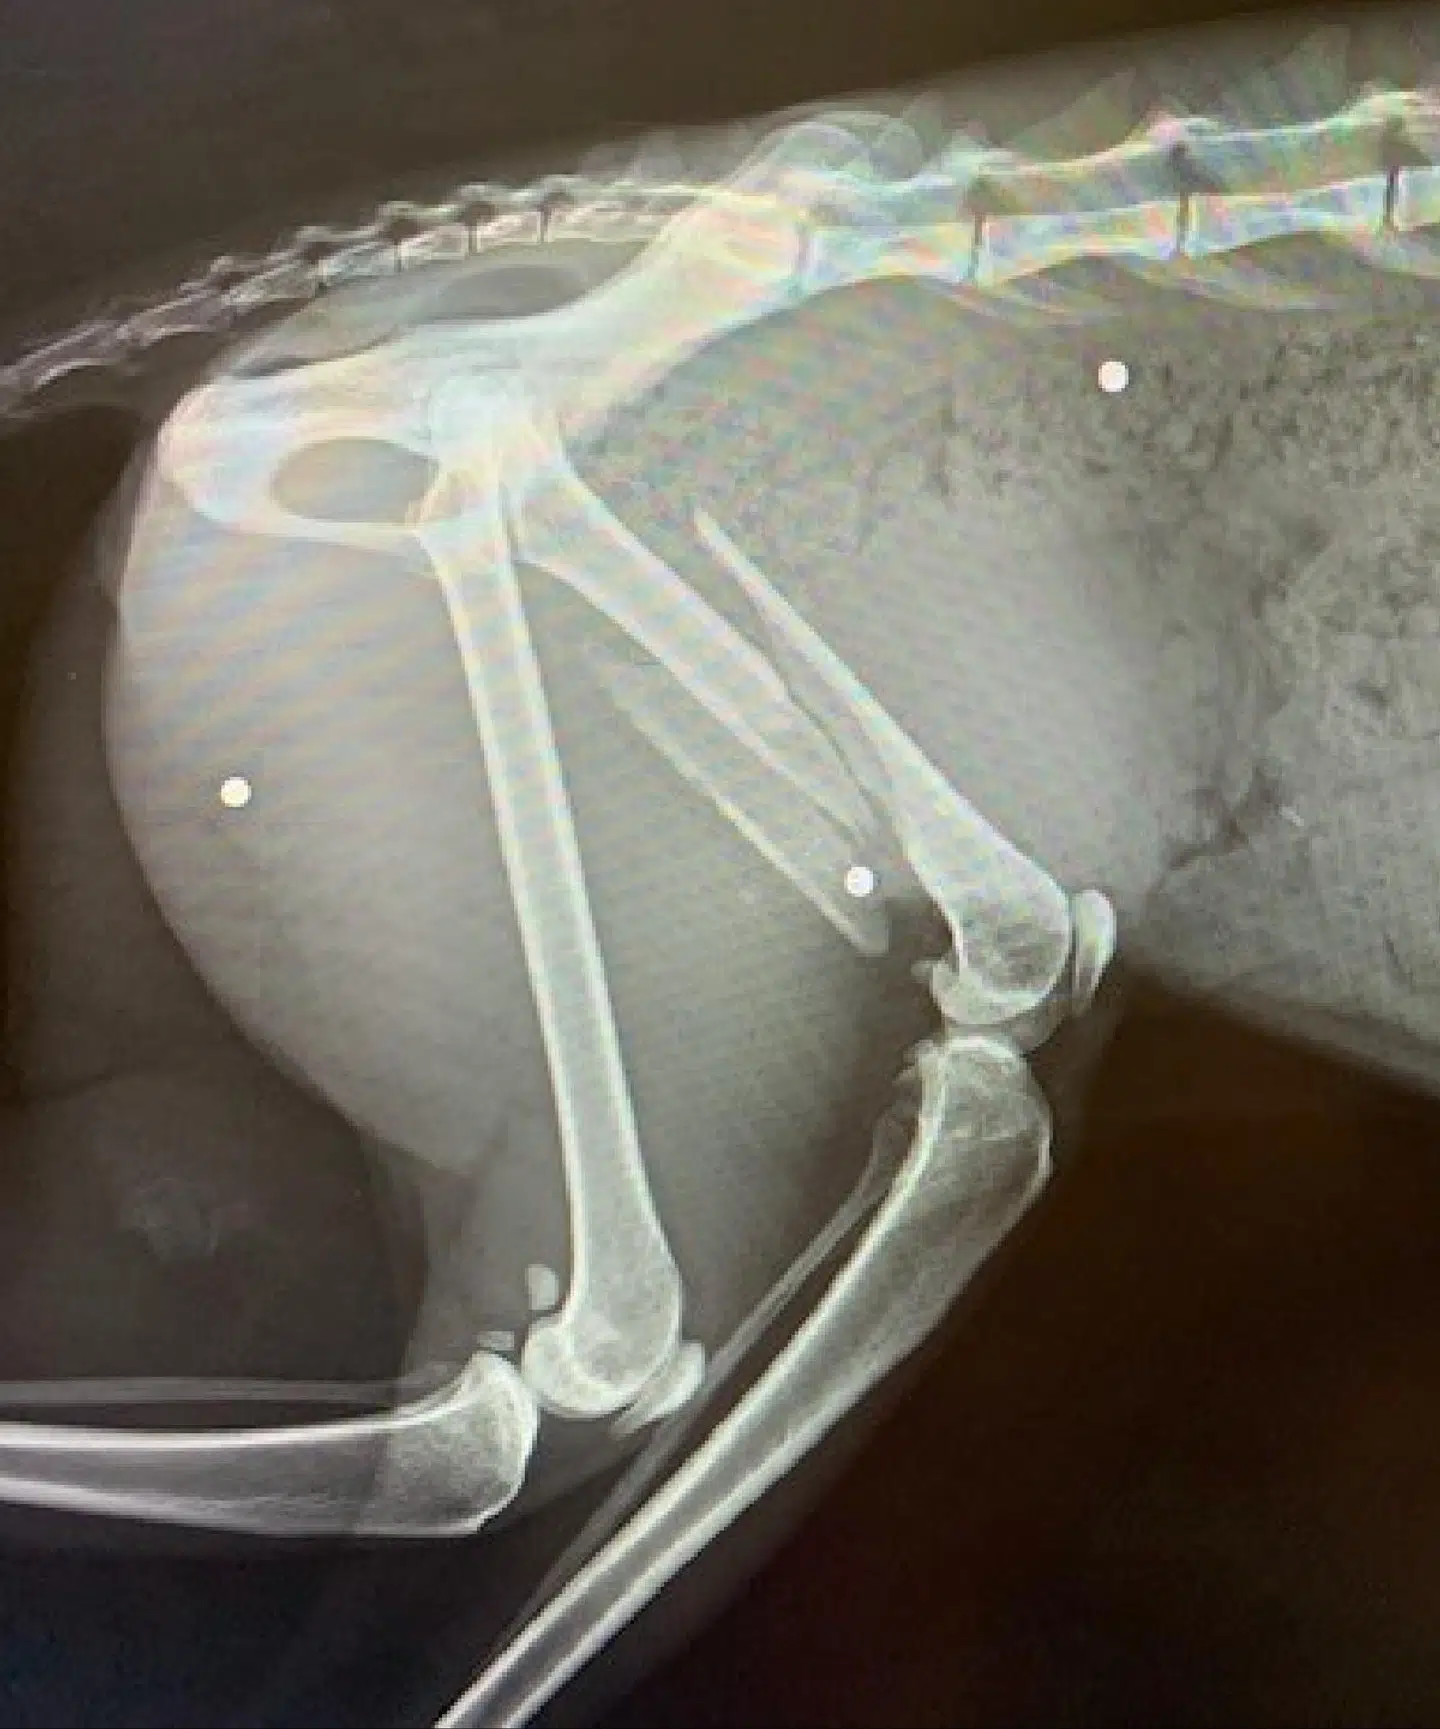

»Det viste sig, at katten, som har fået navnet Feline, var blevet skudt med hagl. Der blev fundet hagl i brystpartiet, i hoften og to i det ene lårben, hvilket havde forårsaget et kompliceret brud på lårbenet.«